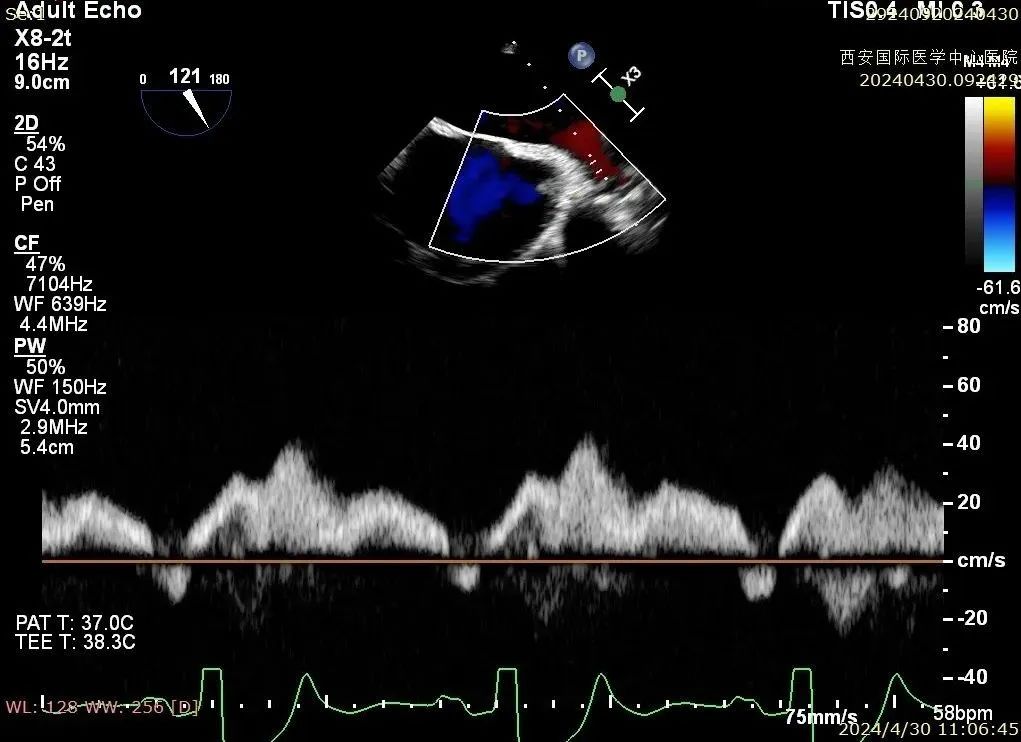

经心脏瓣膜介入团队评估后,决定先于2区植入一枚二尖瓣夹,后根据反流情况,考虑是否植入第二枚夹子。在DragonFly™精准操作下,最终患者术后反流降至1+,跨瓣压差为2mmHg,肺静脉逆流消失。

术后二尖瓣反流评估

术后结果

心脏瓣膜介入团队术中在2区植入一枚二尖瓣夹,关闭二尖瓣夹时时刻关注瓣叶张力,并随时释放张力。患者术后反流降至1+,跨瓣压差为3mmHg。